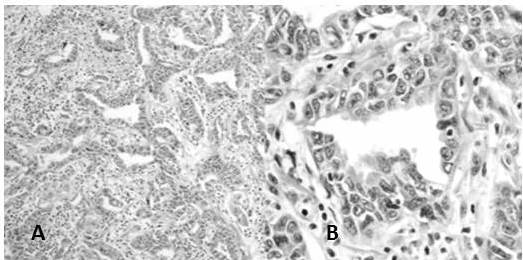

En la reclasificación los casos de ADC estuvieron representados por: ADC patrón predominantemente sólido 57,3 % (Figura 3 y 4), ADC patrón acinar 18,2 % (Figura 5) y en menor frecuencia ADC con patrones mixtos como: patrón predominantemente sólido y acinar 3,6 %, ADC patrón predominante sólido con células en anillo de sello 2,7 %, ADC patrón predominante acinar y micropapilar (Figura 6), patrón predominantemente acinar y sólido, papilar y acinar y patrón predominantemente papilar (Figura 7) cada uno con 1,8 %, asimismo, se encontraron en menor cantidad los siguientes patrones: lepídico no mucinoso (Figura 8) tipo intestinal (Figura 9), mucinoso (Figura 10), y otros patrones mixtos con 0,9 % cada uno (Cuadro 4)

Al reclasificar los casos de ADC de pulmón se encontró el patrón predominantemente sólido 57,3 % como el más común en segundo lugar el ADC patrón acinar 18,2 % y en menor frecuencia: ADC patrón predominantemente sólido y acinar 3,6 %, ADC patrón predominante sólido con células en anillo de sello 2,7 %, ADC patrón predominante papilar, otros patrones mixtos y tipos menos frecuentes. Esto se asemeja a lo encontrado Tsao y col. (10) en el estudio LACE-Bio el cual es el estudio de cohorte multinstitucional más grande hasta el momento en el que se reclasificaron 575 casos de ADC de pulmón para predecir el beneficio de la quimioterapia adyuvante en pacientes sometidos a resección completa obteniendo de igual forma el subtipo predominantemente sólido como el más común con 46 % seguido en secuencia del subtipo predominantemente acinar 26 % siendo este primero equivalente a carcinomas pobremente diferenciados sin ninguna característica de diferenciación reconocible morfológicamente y determinando un peor pronóstico para el subtipo sólido y micropapilar (semejante a lo observado en mama) con una supervivencia más baja y respuesta pobre al tratamiento (10) . De forma similar Warth y col. (19) reclasificaron 100 casos de ADC pulmonares con el fin de determinar la variabilidad inter-observador de la clasificación propuesta por IASLC / ATS / ERS para los ADC pulmonares obteniendo de igual manera el subtipo predominantemente sólido como el más frecuente (37 %), seguido de acinar (35 %), lepídico (20 %), papilar (5 %) y micropapilar (3 %) este resultado de igual forma se asemeja al nuestro con una población similar. Análogo a nuestro resultado también Warth y col. (20) realizan otro trabajo de investigación reclasificando 40 casos de ADC pulmonar con el propósito de determinar la concordancia teniendo en cuenta la nueva clasificación y encontró el subtipo predominantemente sólido, más frecuente con mayor nivel de concordancia.